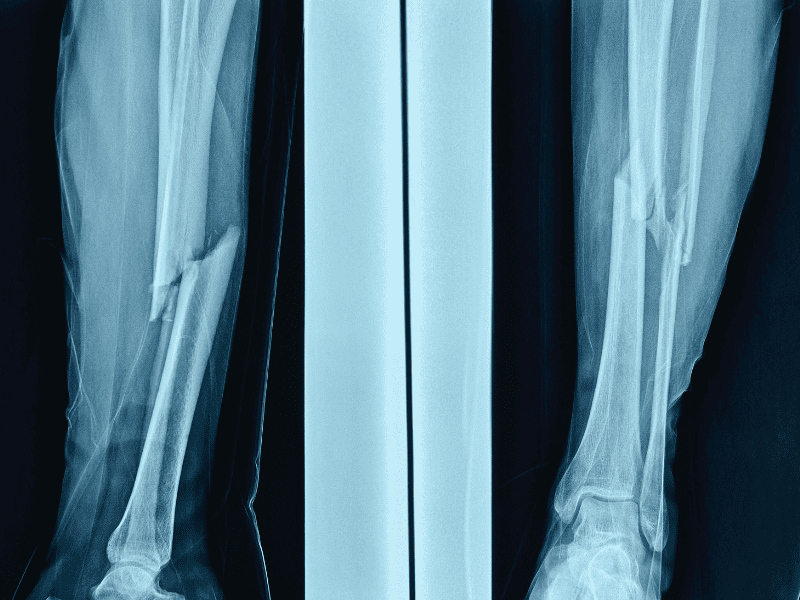

- Diagnostic radiologique détaillé : il permet de confirmer la fracture et d’en préciser la nature. Des examens complémentaires (IRM ou scanner) peuvent être prescrits pour détecter d’éventuelles microfractures ou complications.

- Traitement orthopédique ou chirurgical : selon la zone touchée, le médecin peut opter pour une immobilisation (plâtre, attelle) ou une intervention chirurgicale visant à stabiliser l’os avec des vis, plaques ou prothèses.